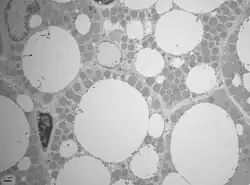

La grasa parda posee un color característico marrón o pardo rojizo debido a que está más vascularizada que la grasa blanca. Por otra parte cuenta con mayor inervación del sistema nervioso simpático y parasimpático. Los adipocitos que la forman tienen mayor número de mitocondrias que la grasa blanca y son más pequeños, de alrededor de 50 micras de diámetro. El citoplasma de estas células contiene numerosas vacuolas de tamaños diferentes, por ello la grasa parda se llama también multilocular.[1]